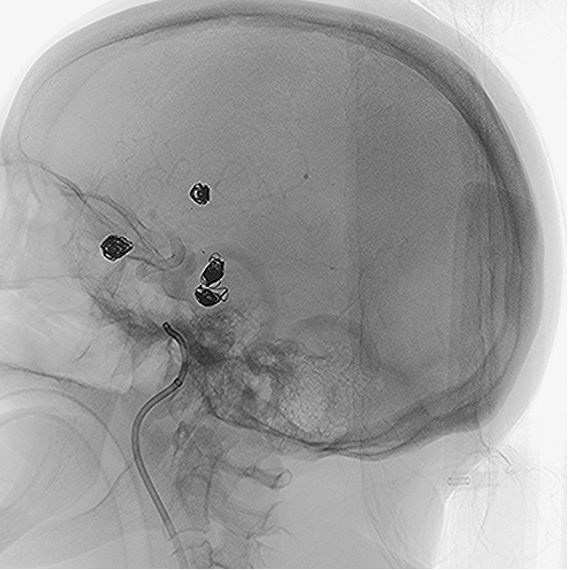

• The NUVA flow diverter demonstrated excellent wall apposition without complications.

• Post-surgery, branch vessels were fully preserved, and the patient’s recovery was smooth with no adverse events.